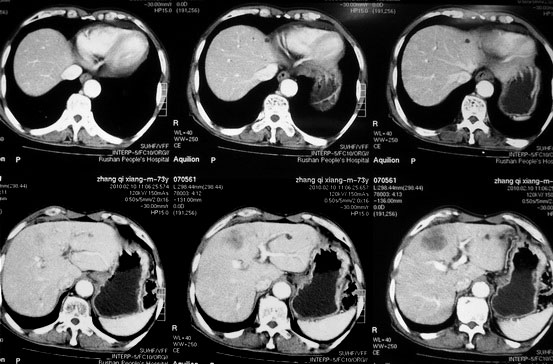

肝胆管细胞癌

患者AFP正常,无肝病病史。CA199 1000ng/ml,CEA偏高。血象WBC正常,N偏高。

这个病人是有病理的,做了肝活检,初八出结果。

请大家再看看,给个意见,谢谢。

化脓性胆囊炎累及肝脏;胆管细胞癌;肝转移瘤

活检病理

:是

胆管细胞癌

。

这个病人开始就是主要鉴别的肝脓肿和胆管细胞癌。可是增强后环征也不明显,占位内造影也非常不明显。这种情况怎么判断?谢谢大家。

病灶强化幅度较轻,低密度坏死区内见无定形高密度影,是其特点。